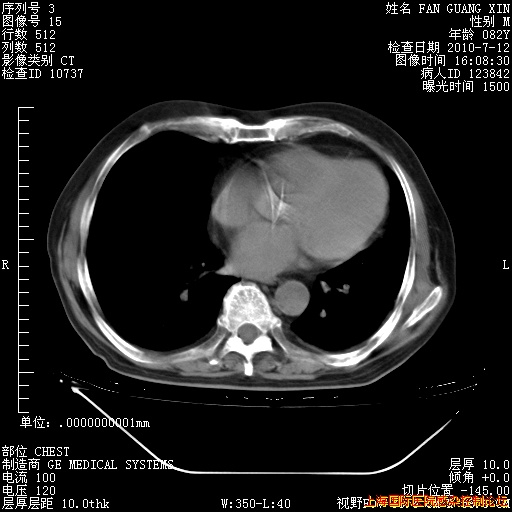

今天复查CT

今天CT

整整相隔30天的肺部CT好像有所好转啊。甲强龙减量第3天,需要观察体温。

海管,自昨日你和我通完话后,不知您岳父消化道症状有无缓解?体温怎样?阅读7.12日胸部ct,个人认为目前激素治疗是有效的,甲强龙减量是适宜的。因在抗痨治疗,需密切观察肝功、肾功能和血常规。不过,老年、长期住院和大量使用激素,很担心菌群失调发生